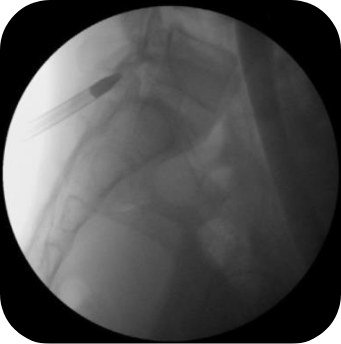

PELD

척추내시경

이 수술법이 처음 나온 지는 20년이 넘었습니다만 최근 들어 기기와 기술의 발전으로 각광을 받게 되었습니다. 피부에 약 7 mm 크기의 내시경을 넣어 수술을 하는 것으로 수술 후 회복이 매우 빠르다는 장점이 있습니다. 과거에는 터져 나온 디스크를 처리하지 못하는 한계를 보였으나 이제는 많이 발전하여 디스크의 여러 유형을 처리할 수 있어 수술의 성공률이나 환자의 만족도도 많이 높아졌습니다.